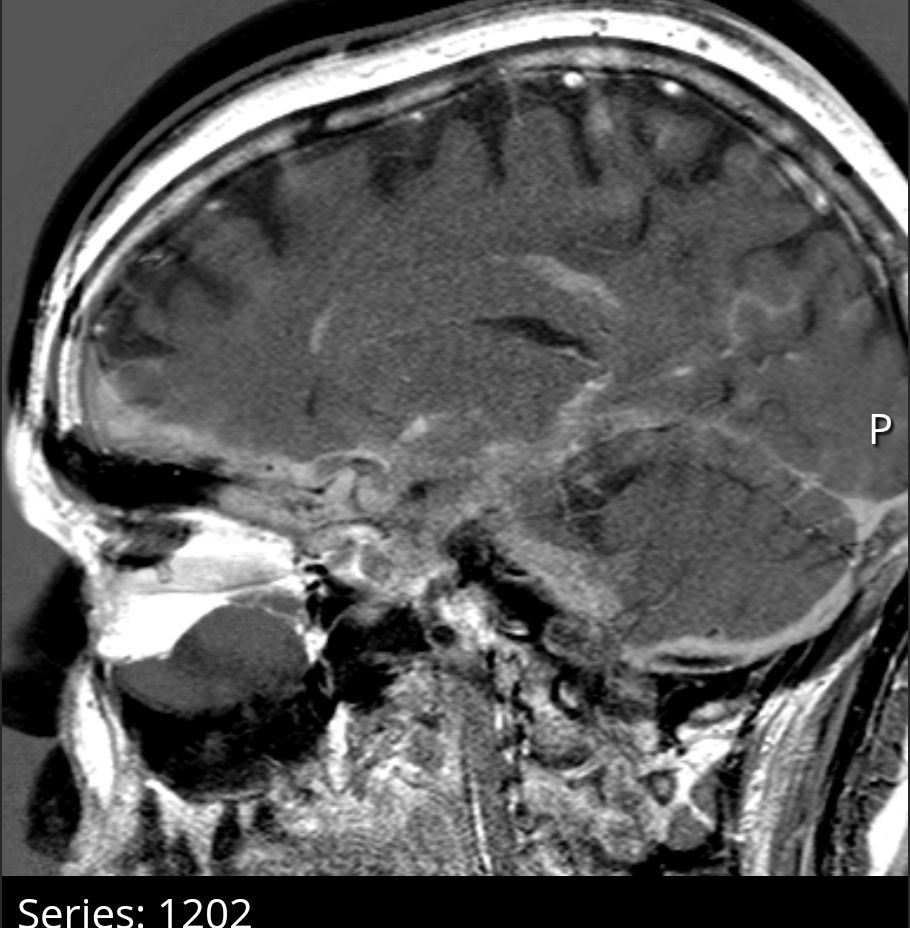

I call this series- 32, or "It's just hard being a single woman at your age."

After horrific trauma, I came back to social media specifically to remind myself that not all doctors are so awful. Thanks for the reminder, they're not all that bad. I cannot tell you the power of feeling heard.